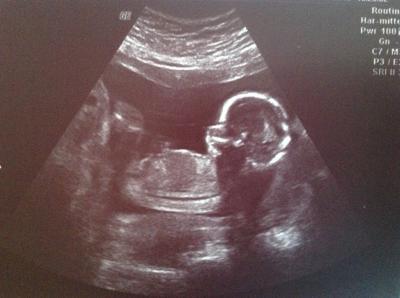

Huhu, War morgens beim FA.. Mein Krümelchen geht es gut, hat sich zeitgerecht entwickelt:) Und da der FA den Hoden bei dem kleinen gesichtet hat, wird es ein Junge! :) Ich hab mir zwar eine Prinzessin gewünscht, aber auf einen Jungen freu ich mich auch, Hauptsache gesund!:) lg Christina

Bild zu Outing:) - Forum für August - Mamis